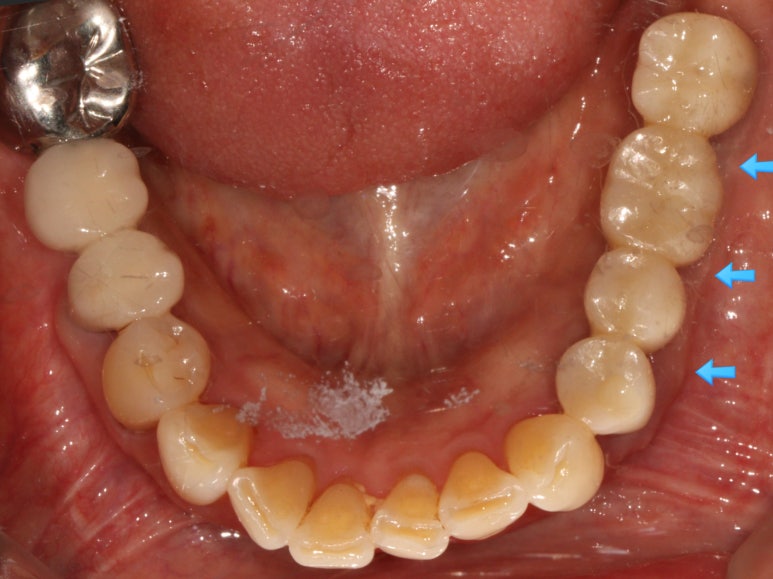

왼쪽 아래 어금니의 임플란트 보철물을 모두 만들고 나서의 임상 사진입니다.

자세히 보시면, 맨 뒤 어금니의 바깥쪽으로 단단하게 보이는 부착치은 (각화치은)이 잘 생착되어 있는 것을 보실 수 있어요!!

비록 많은 양은 아닙니다만,

이 최소한의 2-3mm 폭의 단단한 잇몸은

편하게 양치질을 하게 해주고, 임플란트 주변에 음식물이 끼는 것을 최대한으로 막아준답니다.

그래서 임플란트 주위염의 발생 가능성을 현저히 낮추고, 결과적으로 어금니 임플란트를 오래 쓸 수 있게 해주죠.

치료 완료 후 단단한 잇몸과 볼점막의 경계인 MGJ를 화살표로 표시해 보았는데요,

처음 오셨을 때의 사진을 참고해보시면 이해가 편하실거에요.

아무 치료도 하지 않고 브릿지로 치료가 되어있던 부분은 단단한 잇몸이 하나도 없이 대부분 볼점막의 경계를 갖고 있습니다만,